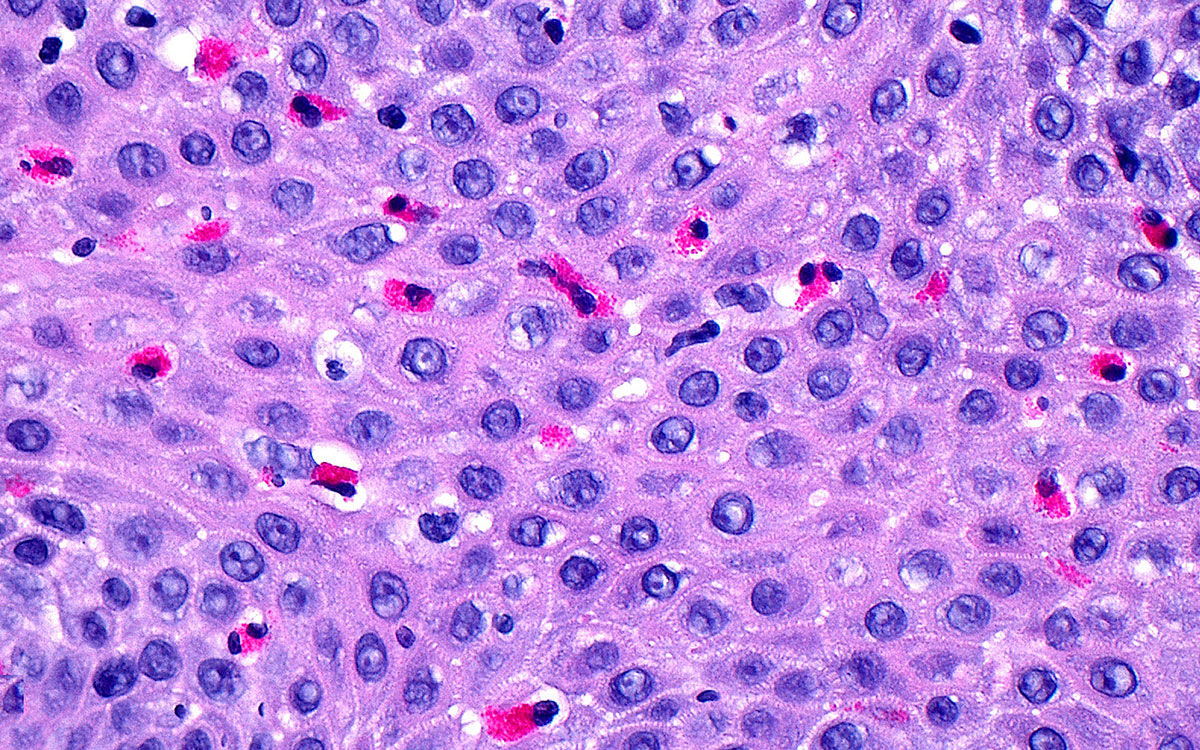

Lysmikrografi av spiserørsepitel (overflaten) med et stort antall eosinofile hvite blodceller. Foto: Science Photo Library /…

Lysmikrografi av spiserørsepitel (overflaten) med et stort antall eosinofile hvite blodceller. Foto: Science Photo Library / NTB